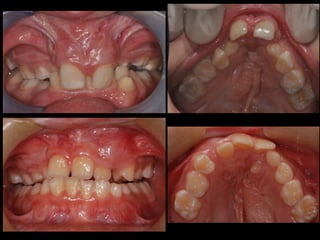

Dental anomalies in Cleft lip and palate patients

• The incidence of dental anomalies is

54%(15% normal population)

• Missing teeth

• Supernumerary

• Enamel hypoplasia

• Morphology anomalies

• Impacted teeth (1

• Missing upper lateral incisor (30-50%)

⬥In deciduous dentition some teeth could be smaller in

the cleft side

⬥Males- laterale incisor and second molar

⬥Females - central and lateral incisors

!

⬥In permanent dentition always lateral incisor

congenitally missing